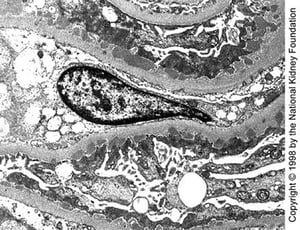

Phức hợp miễn dịch được quan sát thấy dưới dạng các chất lắng đọng dày đặc trên kính hiển vi điện tử (xem hình Đặc điểm kính hiển vi điện tử trong các bệnh cầu thận miễn dịch). Các lắng đọng đặc dưới biểu mô xuất hiện ở giai đoạn sớm với các gai nổi lên ở lớp sáng giữa các lắng đọng. Sau đó, các lắng đọng xuất hiện trong màng đáy cầu thận (GBM) và dày lên rõ rệt. Lắng đọng IgG dạng hạt lan tỏa xuất hiện dọc theo màng đáy cầu thận không kèm theo sự tăng sinh tế bào, xuất tiết hoặc hoại tử.

Các chất lắng đọng dày đặc dưới biểu mô có kích thước trung bình được quan sát thấy trên kính hiển vi điện tử truyền qua trong bệnh giai đoạn I muộn (×10.200).

Các chất lắng đọng dày đặc dưới biểu mô có kích thước trung bình được quan sát thấy trên kính hiển vi điện tử truyền qu

Hình ảnh do bác sĩ Agnes Fogo và American Journal of Kidney Diseases' Atlas of Renal Pathology cung cấp (xem www.ajkd.org).